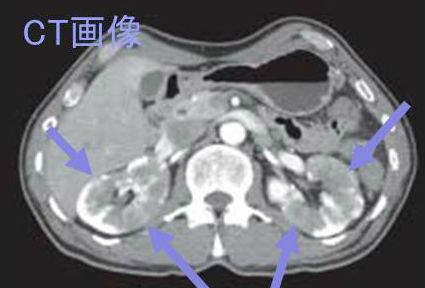

IgG4関連腎臓病は、造影CTで腎実質の多発性造影不領域、びまん性腎腫大、単発性腎腫瘤(hypovascular)を認め、腎臓癌(腎細胞癌)との鑑別が必要になります。